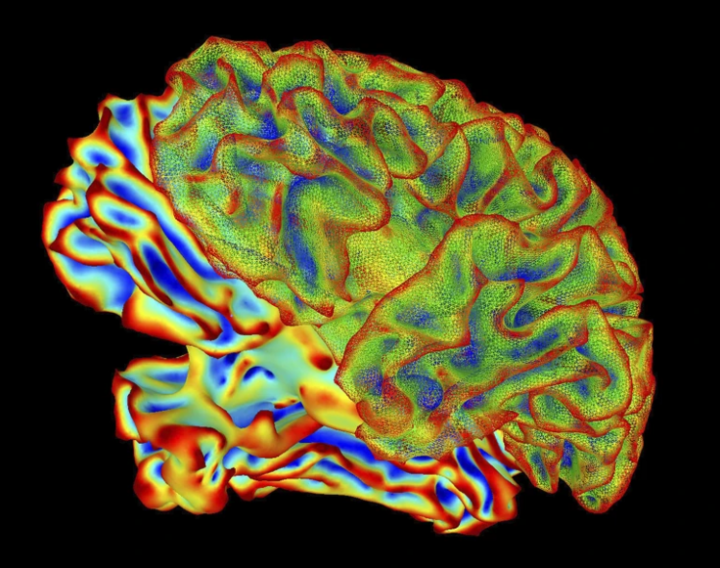

Công nghệ “mind-captioning” có thể giải mã hoạt động não và chuyển đổi những gì con người nhìn thấy hoặc tưởng tượng trong đầu thành câu mô tả bằng chữ với độ chính xác cao. (Ảnh: Nature.com)

Theo nhóm nghiên cứu tại Đại học California, Berkeley (Mỹ), kỹ thuật này sử dụng công nghệ chụp hình não không xâm lấn để ghi nhận hoạt động thần kinh. Sau đó, các nhà khoa học dùng mô hình ngôn ngữ AI tiên tiến để dự đoán và mô tả chính xác điều mà người tham gia đang nhìn hoặc tưởng tượng.